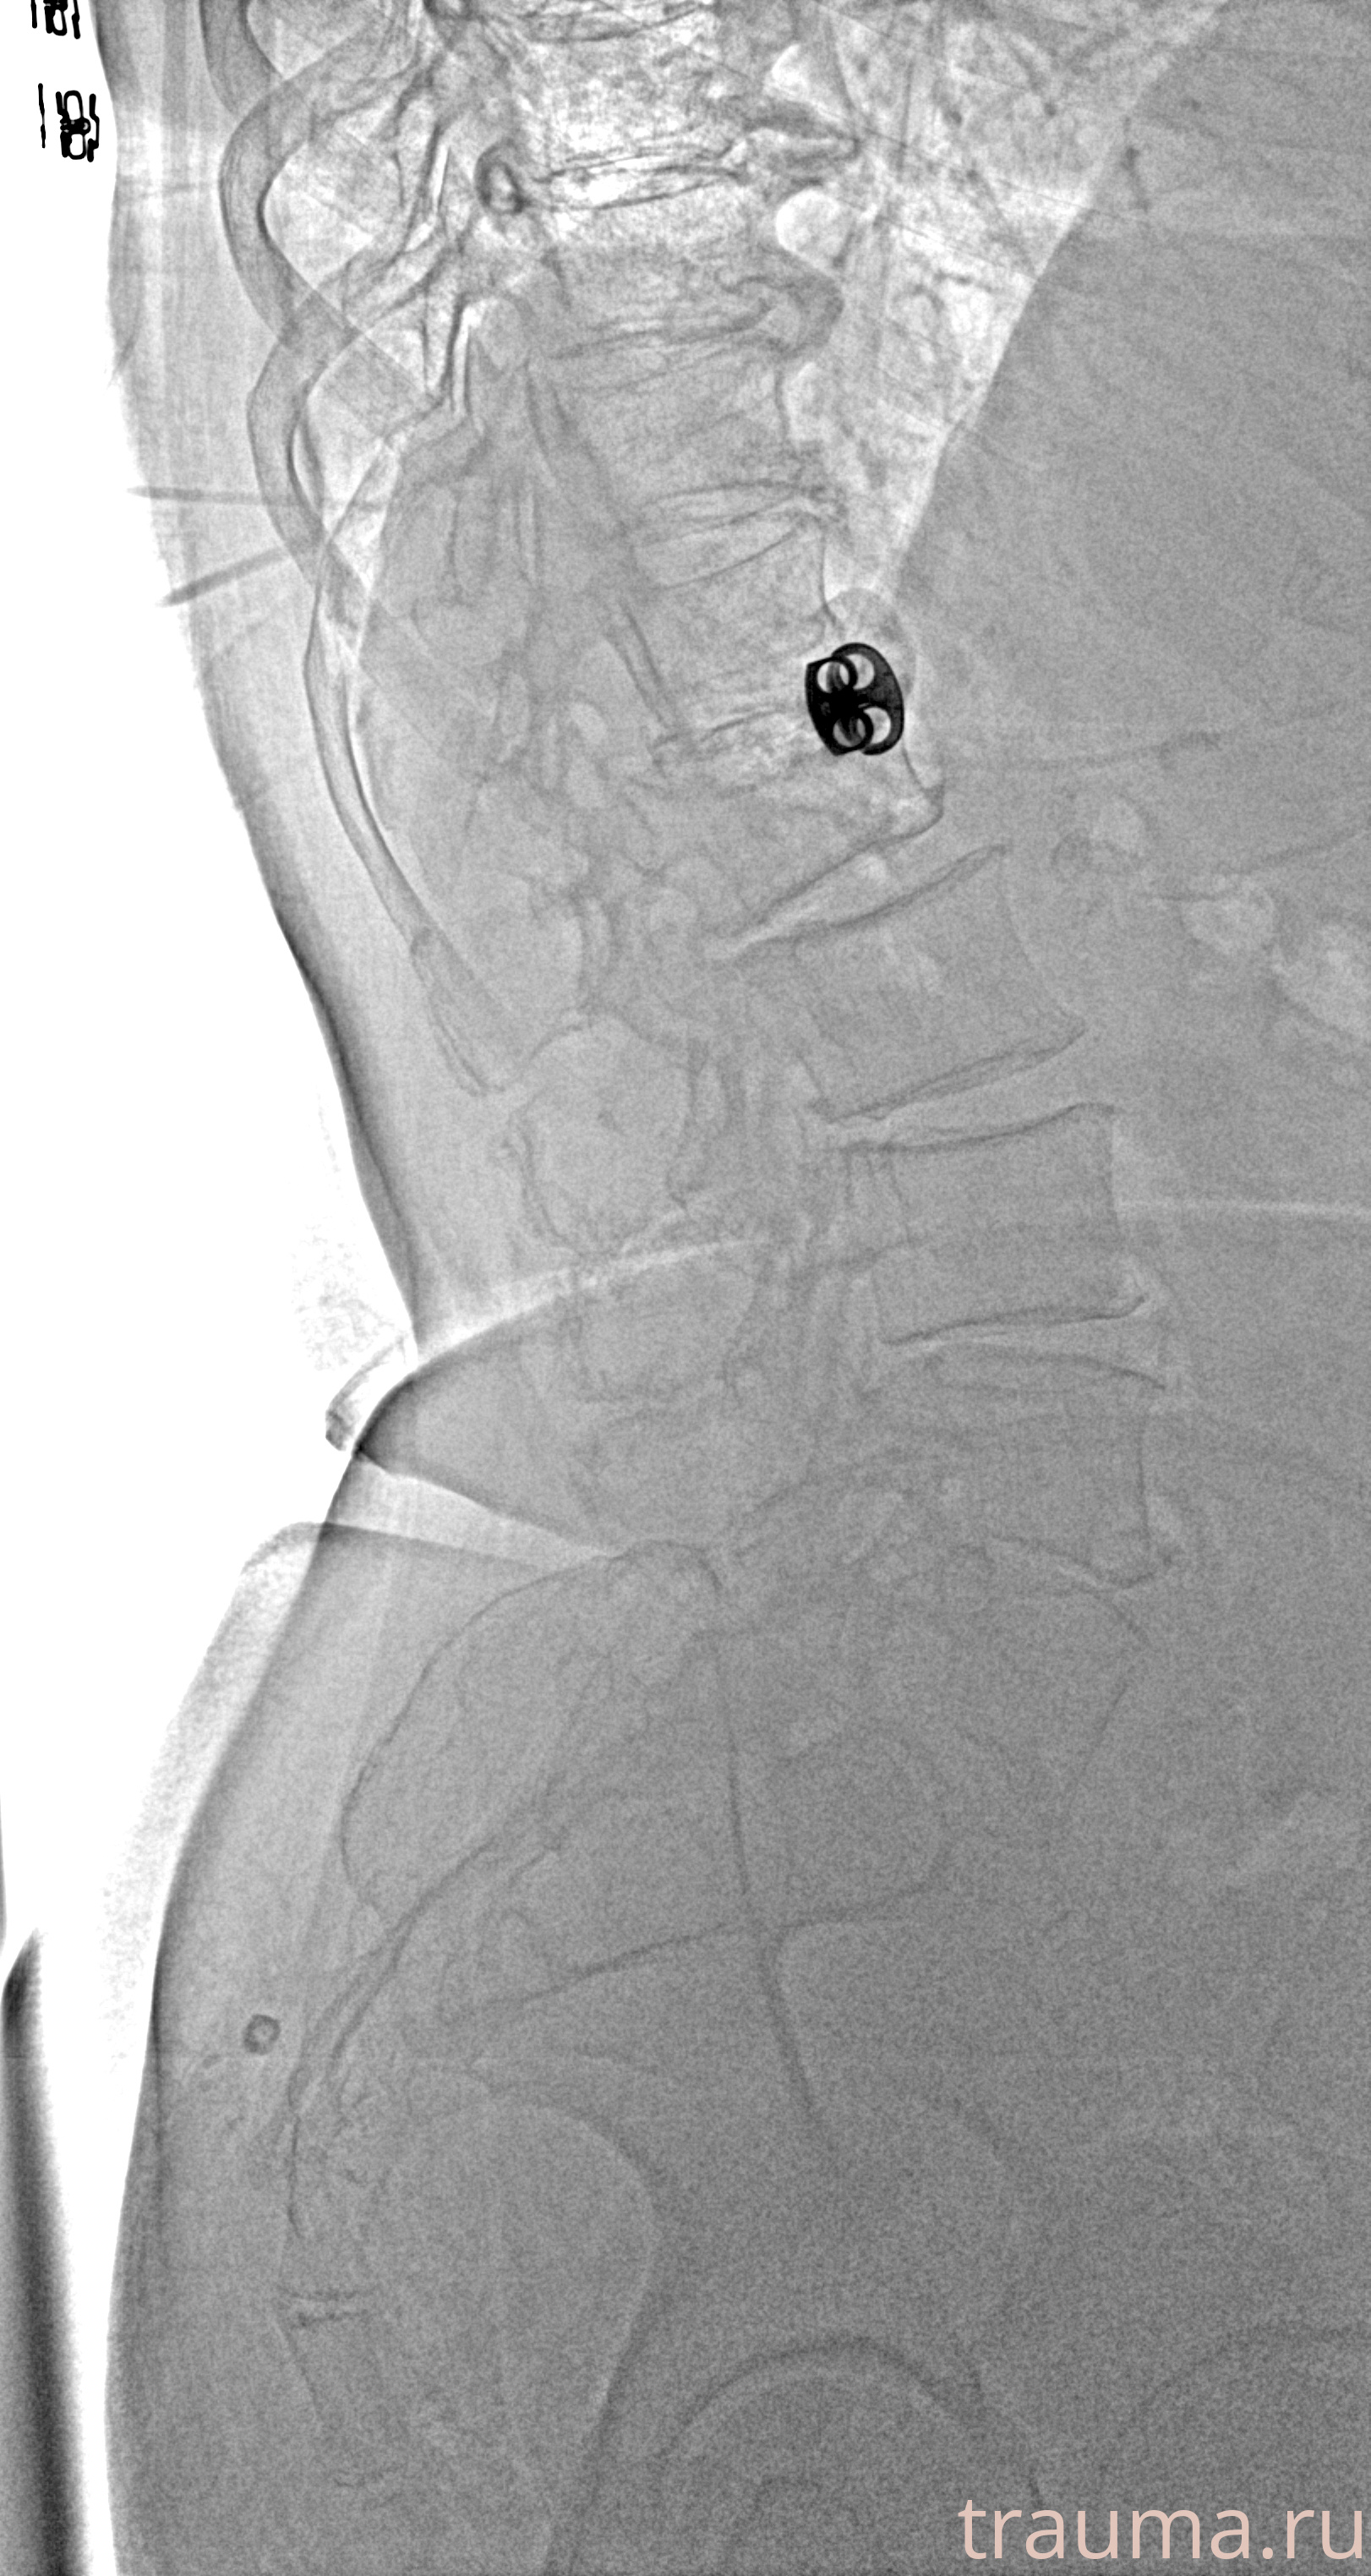

Рентген на дому: по вашему адресу приезжает врач-рентгенолог, травматолог-ортопед с мобильным рентгеновским аппаратом, проводит диагностику травмы или заболевания, делает необходимые рентгенограммы, дает рекомендации по дальнейшему лечению. Получить качественные снимки в домашних условиях возможно благодаря уникальной методике, разработанной МосРентген Центром для института  Склифосовского